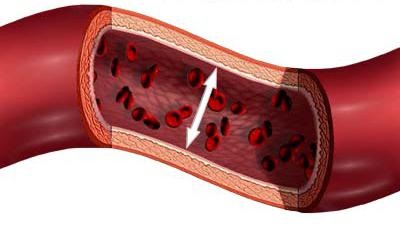

impulzus fogalmak

Impulzus úgynevezett ritmikus oszcillációk átmérőjű erek (artériák), amely által okozott kardiális aktivitást. A mozgás a vér révén az artériák, beleértve az aorta és hajtjuk végre a sebesség 500 mm / s. A vékony erek, kapillárisok, véráramlás jelentősen lelassult (legfeljebb 0,5 mm / s). Egy ilyen kis sebessége a vér áramlását a kapillárisok lehetővé teszi, amely az összes oxigént és tápanyagokat a szövetekben, és megteszi a metabolikus termékek. A vénák, a közelebb a szív, vér áramlás felgyorsul.

Ez a kifejezés a hidrodinamikai nyomás a vér artériák, vénák, kapillárisok. Vérnyomás jelenik eredményeként annak aktivitását a szív, amely szivattyúk vért a hajók, és ezek ellenállnak. Ennek értéke a különböző típusú hajók változik. Vérnyomás növekszik csökkenése szisztolé és diasztolé alatt. Szív kipréseli a vért része, amely kiterjeszti a falak a központi artériák és az aorta. Ez létrehoz egy magas vérnyomás: A szisztolés maximális érték egyenlő 120 Hgmm. Art. és a diasztolés - 70 Hgmm. Art. A diasztolé alatt a kifeszített fal összenyomódik, és ezáltal nyomja a vért a arteriolák és tovább. Amikor a vér átfolyik a kapillárisok fokozatosan csökken a vérnyomás 40 Hgmm. Art. és alatt. Az átmenet venulák vérnyomás csak 10 Hgmm. Art. Ez a mechanizmus okozza súrlódás a részecskék a véredények falai, amelyek fokozatosan késlelteti a vér áramlását. A vénák folytatódott vérnyomásesés. Az üreges vénák, akkor még kissé alacsonyabb a légköri. Ez a különbség a negatív nyomást az üreges vénák és a magas nyomás a pulmonális artéria és az aorta és biztosítja a folyamatos áramlását az ember.